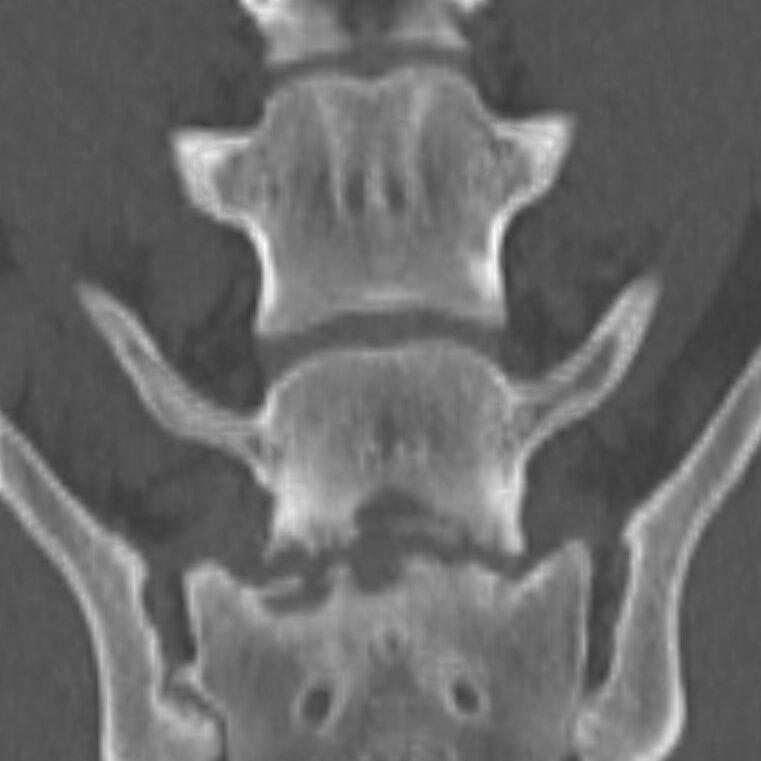

A radiograph of the spine will typically reveal damage to the vertebrae adjacent to the affected disc. The spine can become deformed and undergo bone changes as a result of chronic conditions. Radiographs may not show changes for 3-6 weeks after clinical signs begin, so if the first radiographs are normal, but the clinical signs are progressing, it is sensible to repeat them some time later.

When a typical lesion is detected, radiographs of the entire spine are recommended since some pets have multiple lesions. When a disc is infected, it degenerates and destroys the ends of adjacent vertebrae. There is evidence that these degenerative changes may weaken the vertebral column and make it more susceptible to pathologic fractures, which are caused by infection rather than trauma. As part of the healing process, the body may attempt to bridge the damaged area with bone, which may encroach on the spinal cord and nerve roots, resulting in further complications.

Imaging techniques such as computed tomography (CT) and magnetic resonance imaging (MRI) are more sensitive than plain radiography, particularly when it comes to detecting the problem early on.